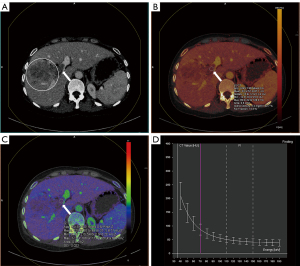

In the ROC analysis (Table 3), the areas under the ROC curves (AUC) for differentiating neoplastic from bland PVT were 0.963, 0.970, and 0.969 for IC, NIC-A, and NIC-V, respectively; and 0.732, 0.952, 0.949, and 0.933 for Rho, Z, DEI, and K, respectively (Figure 4). When the cut-off value for IC was set at 0.950 mg/mL, the diagnostic performance achieved a sensitivity of 96.0% and a specificity of 97.0%. At cut-off values of 19.2% for NIC-A and 24.3% for NIC-V, the diagnostic performance demonstrated sensitivities of 93.2% and 97.3%, and specificities of 96.0% and 91.9%, respectively. When the cut-off values for Rho and Z were set at 37.9 e−/cm3 and 8.05 respectively, the diagnostic performance yielded sensitivities of 68.9% and 96.0% and specificities of 69.7% and 89.9%, respectively. At cut-off values of 0.011 for DEI and 1.10 for K, the diagnostic performance showed sensitivities of 96.0% and 90.5%, and specificities of 87.9% and 88.9%, respectively. Examples of both bland and neoplastic PVT are illustrated in Figures 5,6.